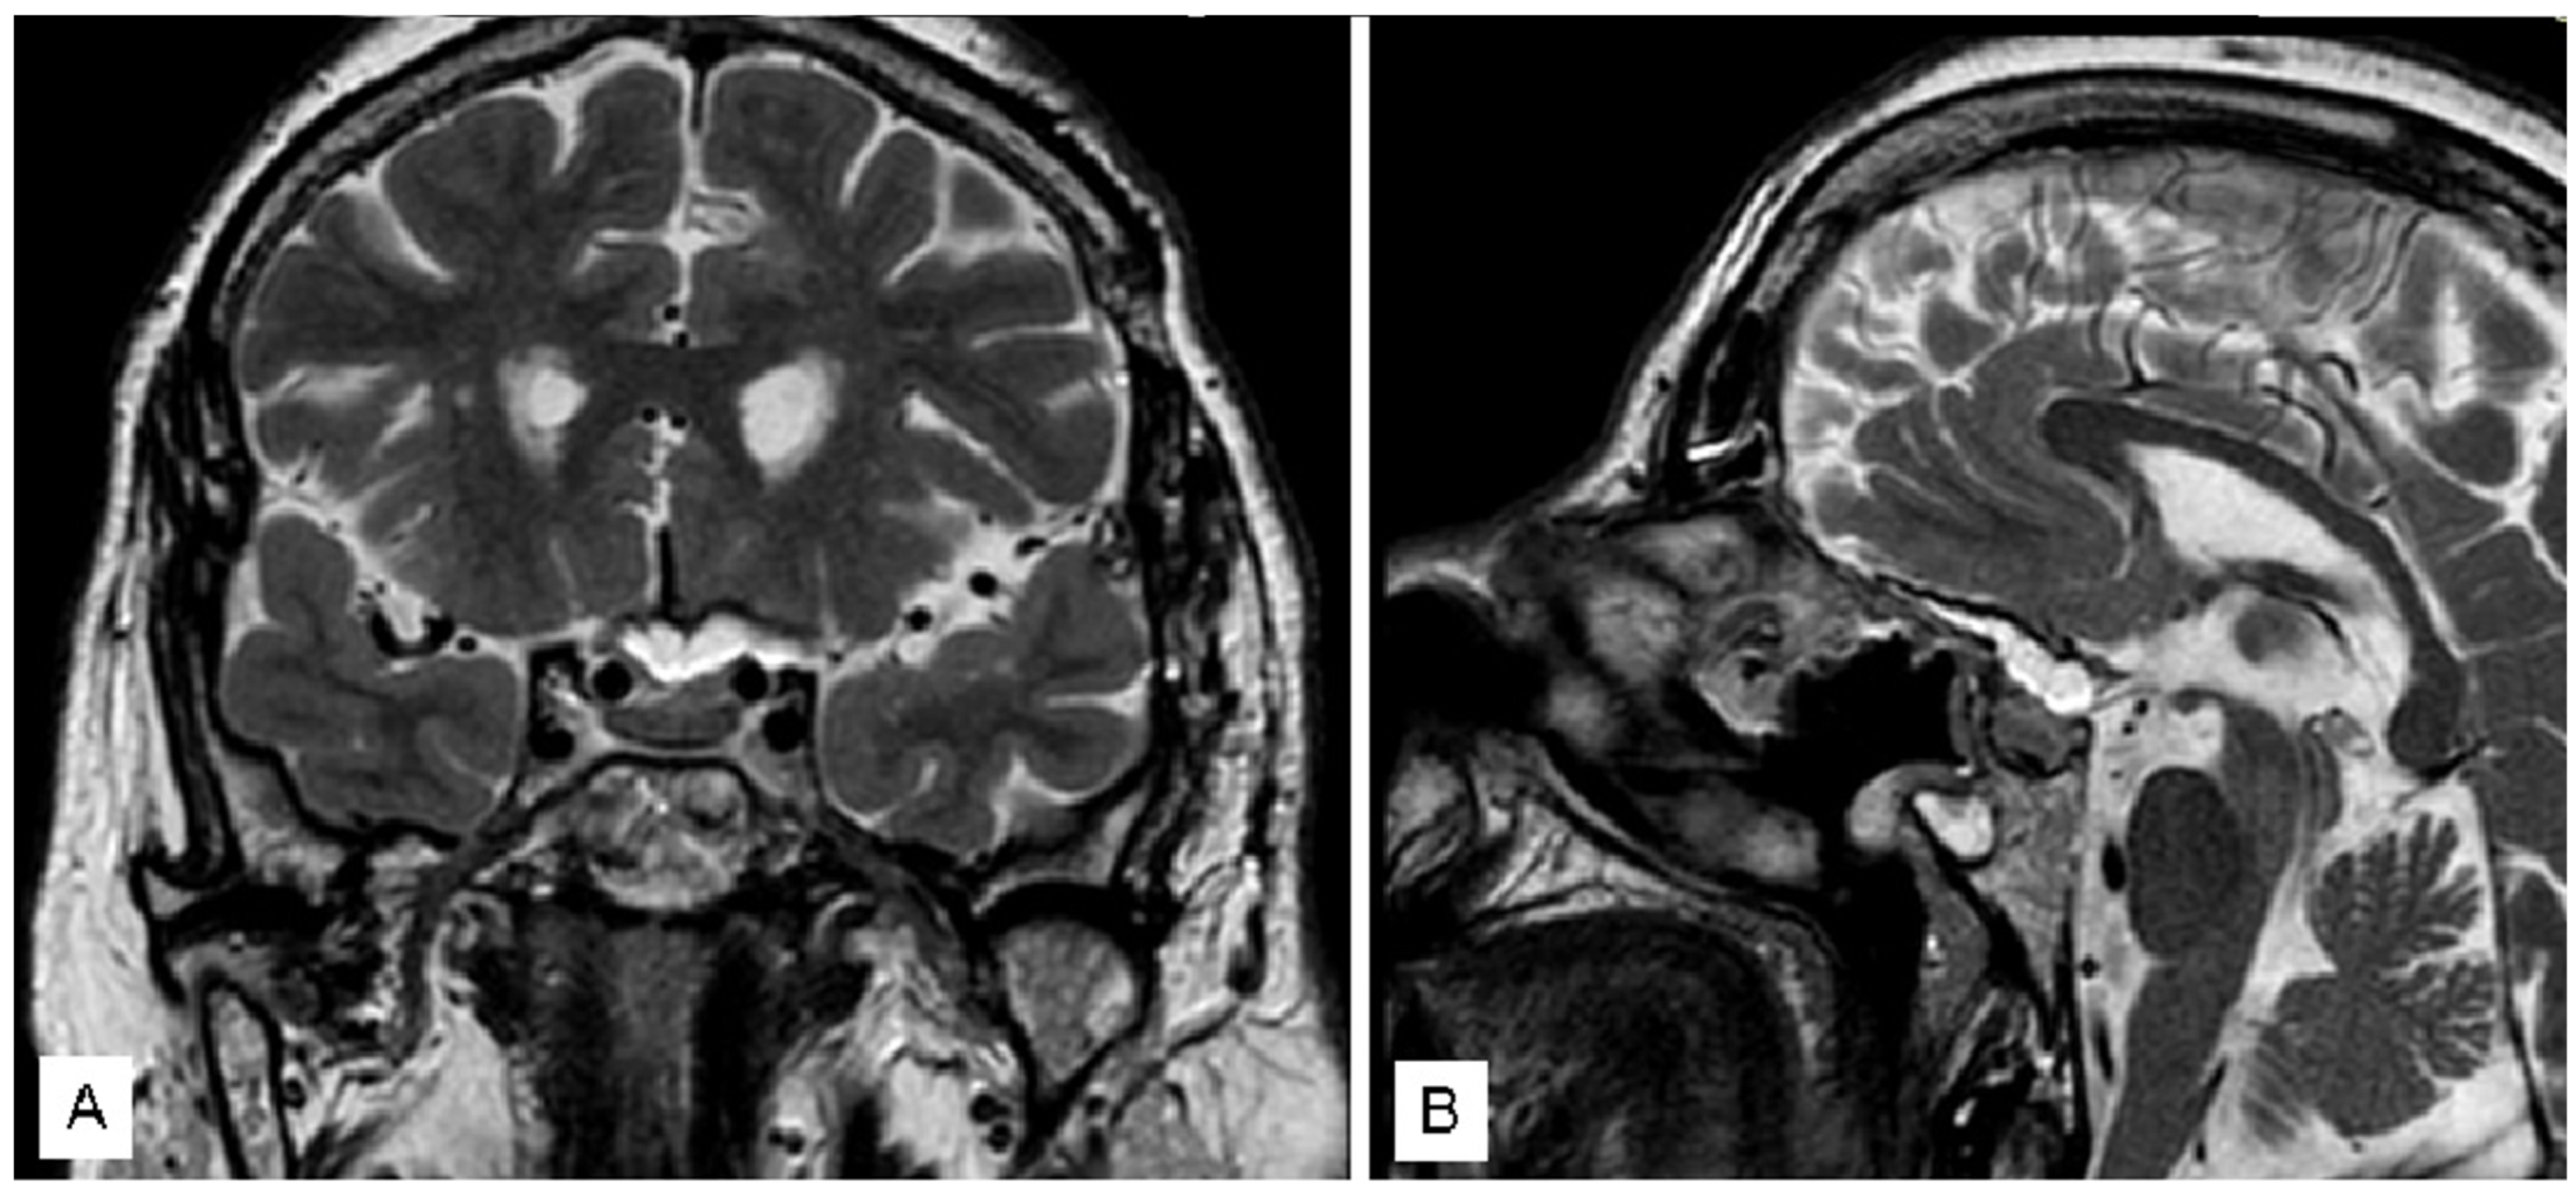

3.1.3. Case 3

4. Discussion